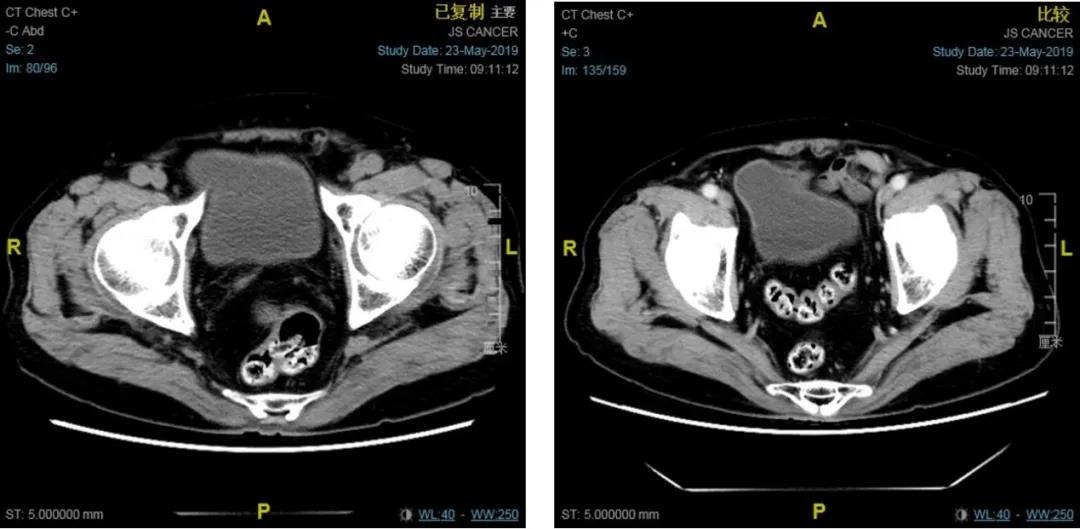

2019年5月23腹部CT:

肝内未见明显异常密度或异常强化影。胆、胰、脾、双肾及双侧肾上腺未见明显异常。

腹腔内及腹膜后未见明显肿大淋巴结。

前列腺约3.8 cm*3 cm(3IM143),右缘饱满,增强后偏右后缘稍强化。

余盆腔内未见明显肿块影,双侧盆壁及腹股沟见小淋巴结。

骨窗:胸2,腰2、4及扫及部分颈椎密度均,可见密度减低及骨质硬化区。

患者入组试验期间,接受阿帕他胺+ADT治疗后,PSA水平持续降低并保持在0.02 ng/ml水平,且ECT示靶病灶数目得到明显改善。2019年5月腹部CT显示患者的情况得到了很好的控制,2年期间并未发生进展。且治疗期间患者依从性良好,无严重不良事件发生。这均证明阿帕他胺+ADT治疗可以显著推迟疾病进展和进入mCRPC时间、提高生存获益。